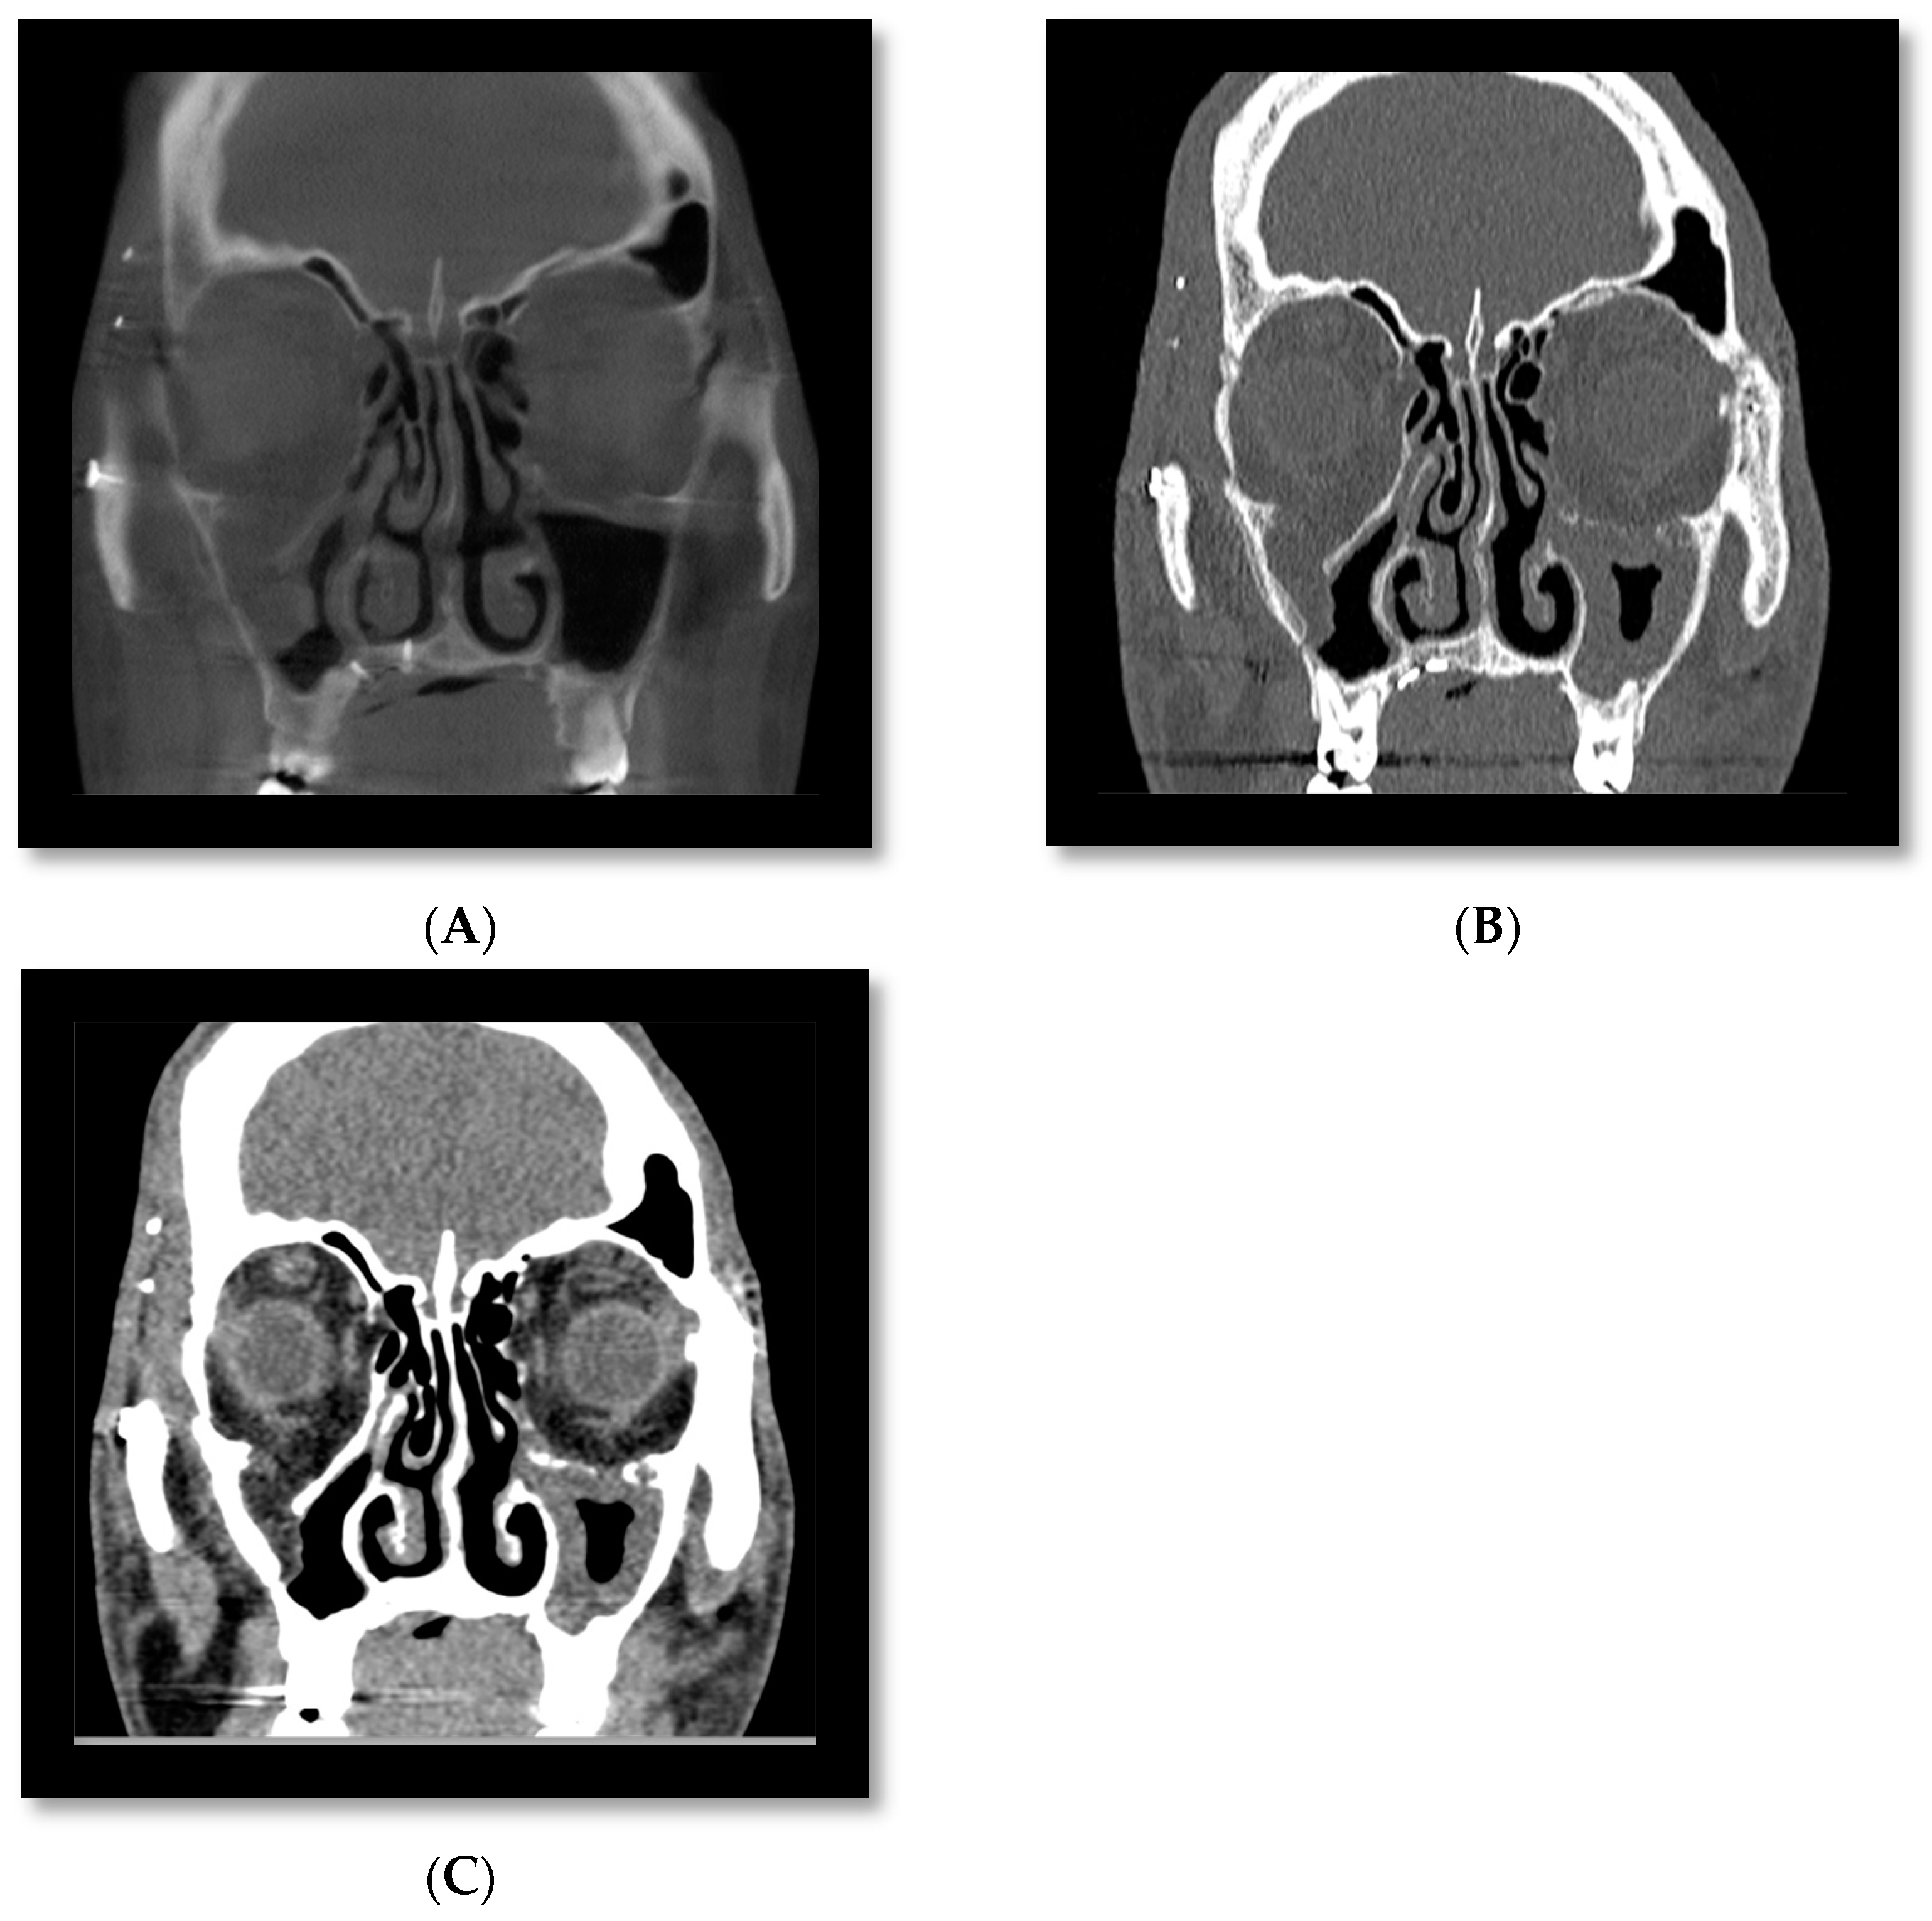

3.4. Cone Beam CT for Assessment of Orbital Fractures

- Brisco, J.; Fuller, K.; Lee, N.; Andrew, D. Cone beam computed tomography for imaging orbital trauma—Image quality and radiation dose compared with conventional multislice computed tomography. Br. J. Oral Maxillofac. Surg. 2014, 52, 76–80. [Google Scholar] [CrossRef]

- Roman, R.; Hedeșiu, M.; Fildan, F.; Ileșan, R.; Mitea, D.; Dinu, C.; Băciuț, M. The use of reformatted Cone Beam CT images in assessing mid-face trauma, with a focus on the orbital floor fractures. Clujul Med. 2016, 89, 519–524. [Google Scholar] [CrossRef]